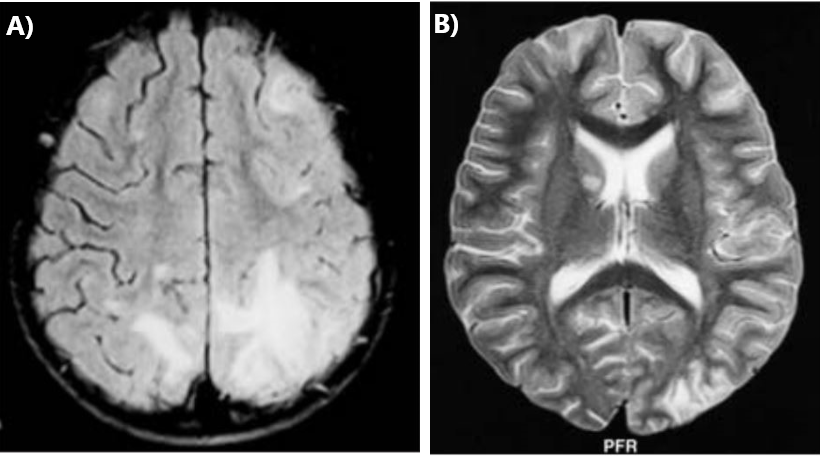

Por otro lado, las principales afectaciones neurológicas que se han visto a lo largo de la enfermedad se concentran en los múltiples eventos isquémicos causados por la inflamación de venas capilares del cerebro. Siendo peligrosos por la severidad de la enfermedad. Así, se ha observado el desarrollo de vasculitis cerebral por púrpura de Henoch-Schönlein.

Y es que, uno de los principales padecimientos es la vasculitis infantil. Factor que se debe a la complejidad de la enfermedad y órganos afectados durante el transcurso de esta.

Así mismo, es importante considerar que al existir una afectación en los riñones de los niños, suele haber también una alteración directa relacionada con la supresión arterial. Pudiéndose generar un evento isquémico en el cerebro del infante (Alvares-Sabin et al., 2000).

- Alvarez-sabin, J., Montaner, J. y Molina, C. (2000). Manifestaciones neurológicas en la púrpura de Schönlein-Henoch: ¿Vasculitis cerebral o leucoencefalopatía posterior reversible? Medicina clínica, 115(17), 677. Doi: 10.1016/S0025-7753(00)71657-5

- Gonçalves, C., Ferreira, G., Mota, C. y Vilarinho, A. (2004). Vasculitis cerebral en púrpura de Schönlein-Henoch. In Anales de Pediatría, 60(2), 188-189. Doi: 10.1016/S1695-4033(04)78246-6